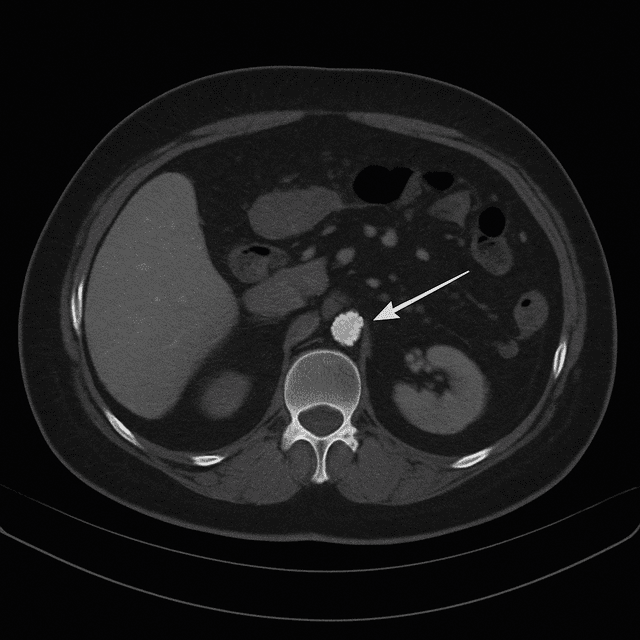

Detects hidden tumors anywhere in the body as small as a few millimeters.